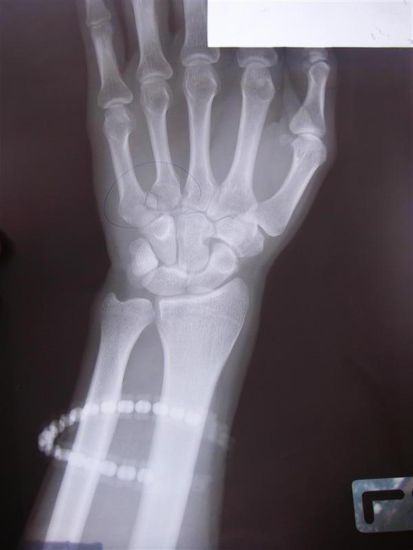

Shaun verfrachtete Jasmin, die unter Schock stand und deren rechter Fuss teilweise bis auf den Knochen abgeschabt war, auf den Beifahrersitz einer netten Pick-Up Fahrerin die Jasmin in ein Krankenhaus brachte. Shaun und ich sammelten die zurueckgebliebenen Teile zusammen, danach musste ich, weil Shaun sich nicht getraute mich hinten aufzuladen, den Roller in meinem momentanen Zustand den Berg hinunter zur naechsten Apotheke fahren (wer immer auch von sich das Gefuehl hat, gut mir Schmerzen umgehen zu koenen, soll doch mal versuchen 20 min lang mit einer gebrochenen Hand (und somit nur mit der Vorderbremse) und einem halb geschaelten Koerper unter der brennender Asiensonne einen sandigen Berg hinunter zu fahren).

Die Bilanz unseres Ausfluges:

Julian:

-Abschuerfungen am rechten Knie, Ober- und Unteschenkel sowie am rechten Unterarm

-"Loecher" in beiden Handballen

-Ganze rechte Schulter/-blatt abgeschaehlt

-Knochenbruch im linken Handteller